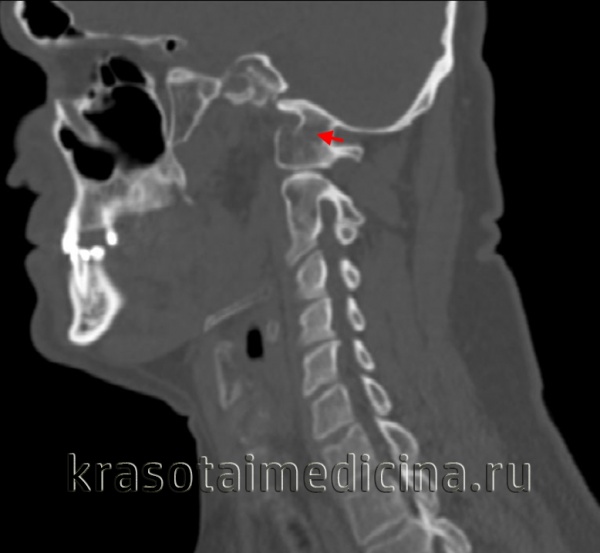

(Слева) На аксиальной КТ в костном окне определяется уменьшение передне-заднего размера на фоне его гипоплазии наряду с расщеплением и срединными дефектами передней и задней дуги. Определяется утолщение и дисплазия зубовидного отростка.

(Справа) На сагиттальной КТ в костном окне у пациента с расщеплением С1 определяется легкая дисплазия зубовидного отростка и патологическая гипоплазия С1 с тяжелым стенозом позвоночного канала. Обратите внимание на сопутствующее нарушение сегментации С2/С3.

(Слева) Аксиальный КТ-срез: уменьшенное в передне-заднем направлении гипопластичное кольцо С1, имеющее характерную конфигурацию «расщепленного кольца», характеризующуюся наличием дефектов передней и задней дуги. Зубовидный отросток утолщен и также диспластичен.

(Справа) На сагиттальном КТ-срезе пациента с расщеплением кольца С1 видны умеренно диспластичный зубовидный отросток и признаки гипоплазии кольца С1, являющиеся причиной тяжелого стеноза спинномозгового канала. Обратите внимание на сочетанное нарушение сегментации С2/3. (Слева) На аксиальном КТ-срезе определяется широкий срединный костный дефект передней и задней дуг атланта. Такой широкий дефект позволяет предположить наличие нестабильности.